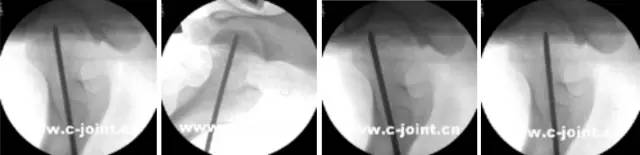

开展关节镜下交叉韧带单、双股解剖重建技术、膝关节多韧带损伤的一期修复重建术、半月板缝合技术、骨软骨移植技术、同种异体移植治疗交叉韧带损伤、双隧道重建交叉韧带、肩关节镜下肩袖修补和SLAP损伤修补术,及肘、踝、腕、髋关节镜术。专业运动员伤病诊治技术、股骨髋臼撞击综合症、股骨头坏死阶梯治疗技术、骨软骨移植技术。

小孔径多孔道低钻速钻孔减压

膝关节镜-前交叉韧带重建